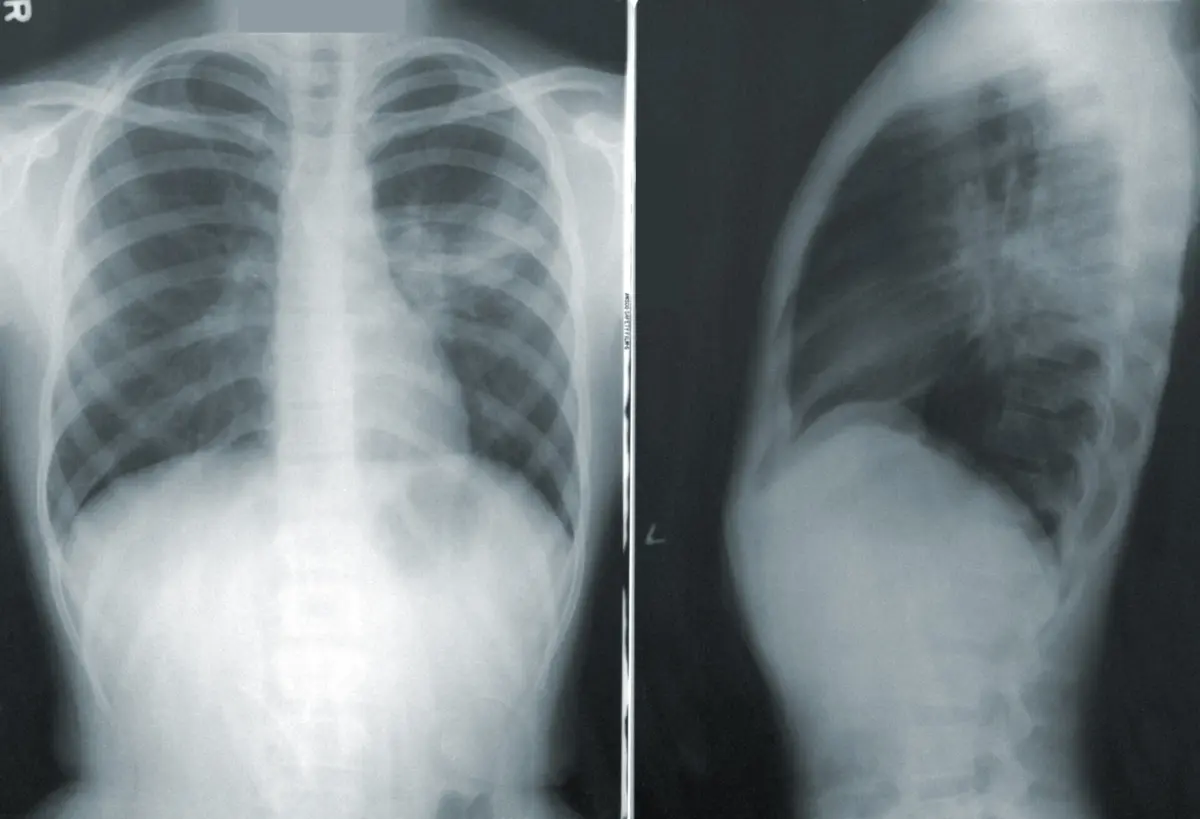

O estudo, que irá iniciar-se na primavera do próximo ano, vai submeter os nove mil indivíduos a espirometrias, o exame que permite diagnosticar a DPOC, e a inquéritos, que vão permitir obter informações muito significativas acerca da saúde respiratória dos portugueses.

"O programa da rede de espirómetros é absolutamente crucial. É um exame em que os serviços de pneumologia podem prestar apoio e, efetivamente, é absolutamente incontornável a presença de espirometrias para o incremento da saúde do respirador e para colocar o diagnóstico desta doença, anualmente, mais próxima da realidade", garante António Morais.